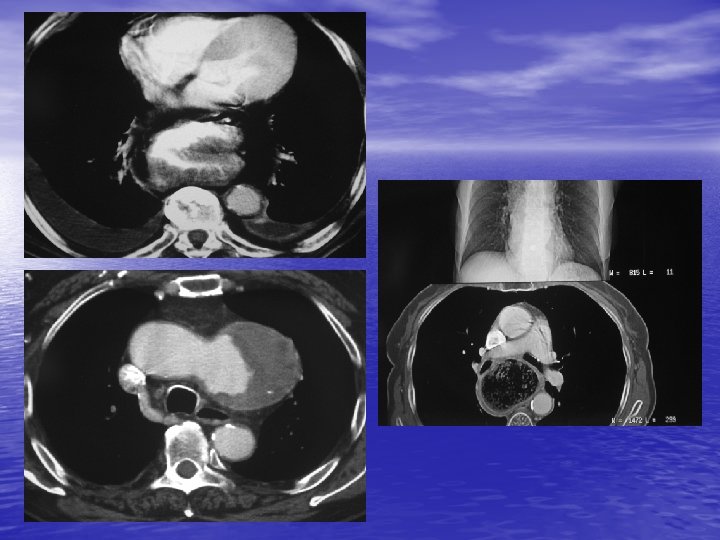

4. MASSES DU MEDIASTIN MOYEN 4. 1. Kyste bronchogénique - 10 % des tumeurs du médiastin. - Bourgeon aberrant détaché de l’ébauche trachéo - -bronchique. Diagnostic fortuit. Rond ou ovale, parfois paroi calcifiée. Densité parfois élevée (lait calcique).

4. 2. Autres tumeurs - Kyste gastroentérique. - Lymphangiome kystique. - Hernie hiatale. - Méga œsophage. - Lésions aortiques : anévrysme de la portion horizontale, malformations.